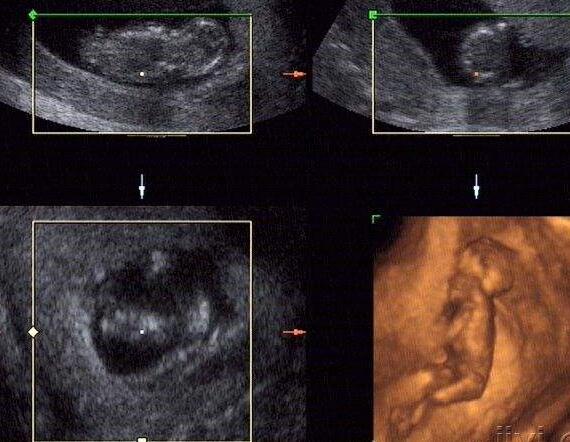

懷孕的前三個月都是懷孕的初期,這時候的寶寶在子宮內膜裡還沒有長穩,也是風險最大的時候。所以這個時期的準媽媽會非常忐忑。